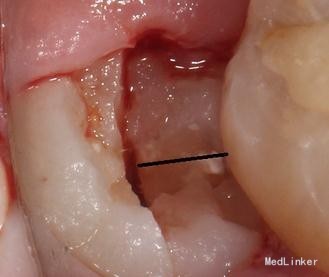

治疗计划:18、28,38拔除。 37重新充填。 48观察。 治疗:28局麻下拔除。 38阻滞下拔除。

拔牙常用牙挺的三步骤、 第一步、楔法:置挺时,插入牙根与牙槽骨之间,然后施力,边旋动,边楔入,使牙在牙槽窝内逐渐松动 ↓ 第二步、推法:将挺刃插在所拔牙牙齿的近中面或颊侧面与牙槽骨之间,使挺刃的凹面朝向根面凸面支靠在颊侧近中牙槽嵴上作为支点。用靠近冠部的挺刃推动所拔牙,使该牙受力后被推向远中或者舌侧而松动,但不包含使牙脱出牙槽的力。 其实说白了推法楔法差不多,只是用力方向幅度大小不同。 楔是向下楔入,推是增大间隙。 第三步、挺法:置放方法与推法一致,只是用力方向变了。向远中面方向旋动牙挺时,使紧贴颈部根面的挺刃向所患牙使力,使其受力后被挺向远中并向合面方向移动。再逐渐加大牙挺旋动的幅度,并将挺刃逐渐向牙槽内插入(配合楔法),牙的松动度也随之增大。最后,使该牙将向合面与远中的合力方向松动脱位。